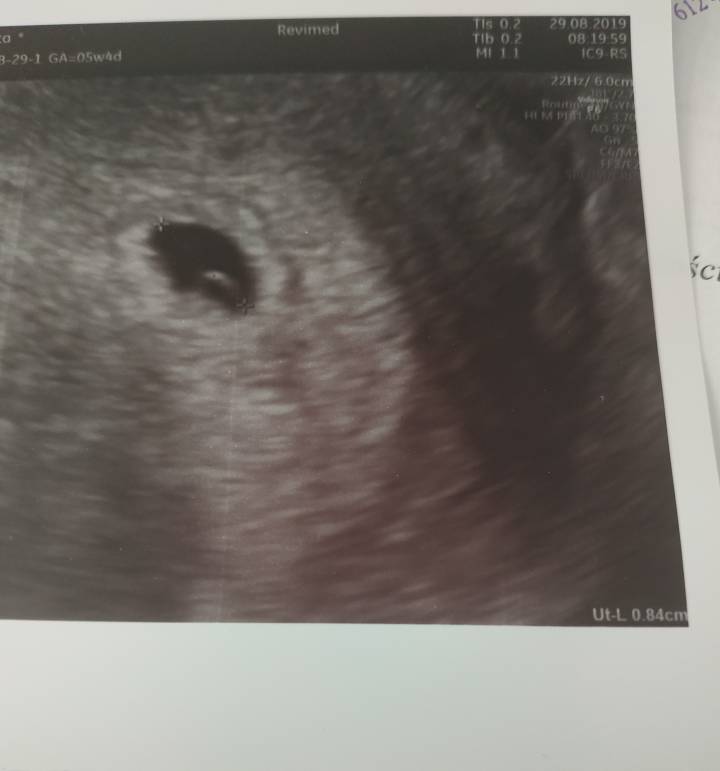

U mnie dzisiaj 5t4d i nie miałam zarodka, ale lekarz mówił , ze wszystko jest dobrze. Za dwa tygodnie mam już zobaczyć serduszko [emoji3590]Zobacz załącznik 1015892Zobacz załącznik 1015893